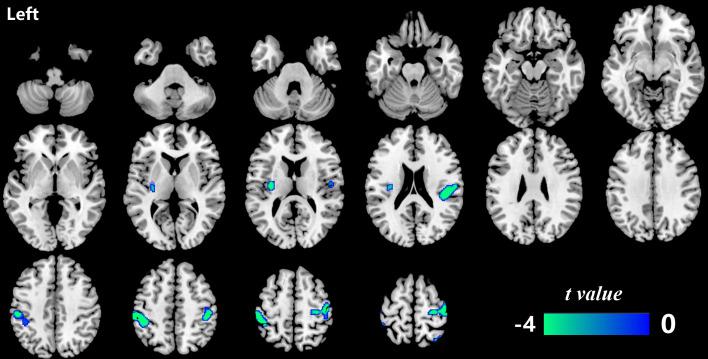

Over 5 years, decreased mReHo:mCBF ratios in patients with T2DM were mainly distributed in four regions, among which the left insula exhibited more severely decreased mReHo:mCBF ratio in patients with T2DM than in HCs, while the left postcentral gyrus, the right Rolandic operculum, and the right precentral gyrus showed no significant intergroup difference. Correlations between the mReHo:mCBF ratio and memory performance were also found in patients with T2DM.

This study suggests that T2DM may accelerate neurovascular coupling impairment in specific brain regions (the left insula), contributing to memory decline. This study implies that the mReHo:mCBF ratio is a potential imaging marker for detecting neurovascular changes.

在 5 年期间,T2DM 患者的 mReHo:mCBF 比值降低主要分布于 4 个区域,其中左侧脑岛的 mReHo:mCBF 比值降低更明显,而左侧中央后回、右侧 Rolandic 岛盖、右侧中央前回在两组间无显著差异。T2DM 患者的 mReHo:mCBF 比值与记忆表现之间也存在相关性。

本研究表明,T2DM 可能加速特定脑区(左侧脑岛)的神经血管耦联损害,导致记忆下降。本研究提示 mReHo:mCBF 比值可能是检测神经血管变化的潜在影像学标志物。